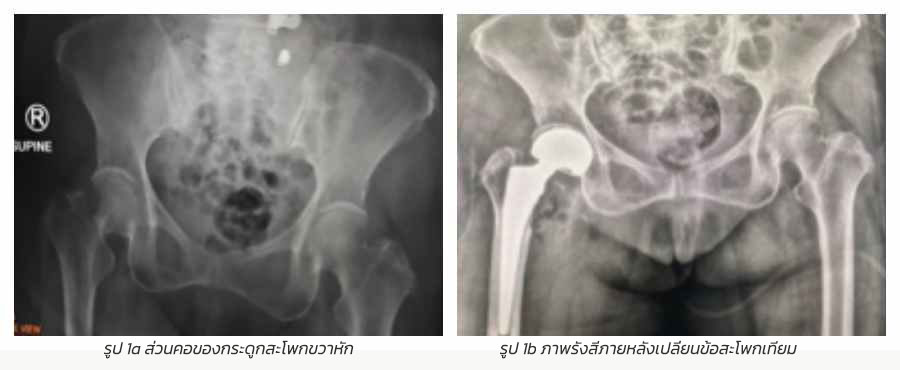

ชนิดของกระดูกสะโพกหัก มี 2 แบบ คือ ส่วนคอของกระดูกสะโพกหัก และส่วนที่อยู่ระหว่างปุ่มกระดูกใหญ่และปุ่มกระดูกเล็กของกระดูกสะโพกหัก โดย

แบบที่ 1 รักษาด้วยการเปลี่ยนข้อสะโพกเทียม สำหรับส่วนคอของกระดูกสะโพกหัก ดังรูปที่ 1a และ 1b